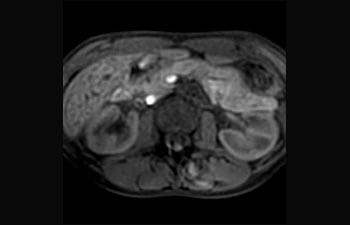

La Sra. Silvia Schiffer, directora y radióloga experta en la clínica Radiologie Schiffer, en Alemania, comparte sus experiencias con el sistema de RM Prodiva 1.5T.

Conozca la opinión de los primeros usuarios de Ingenia Prodiva 1.5T acerca de sus experiencias con el sistema y cómo influye este en su centro de diagnóstico por imagen.